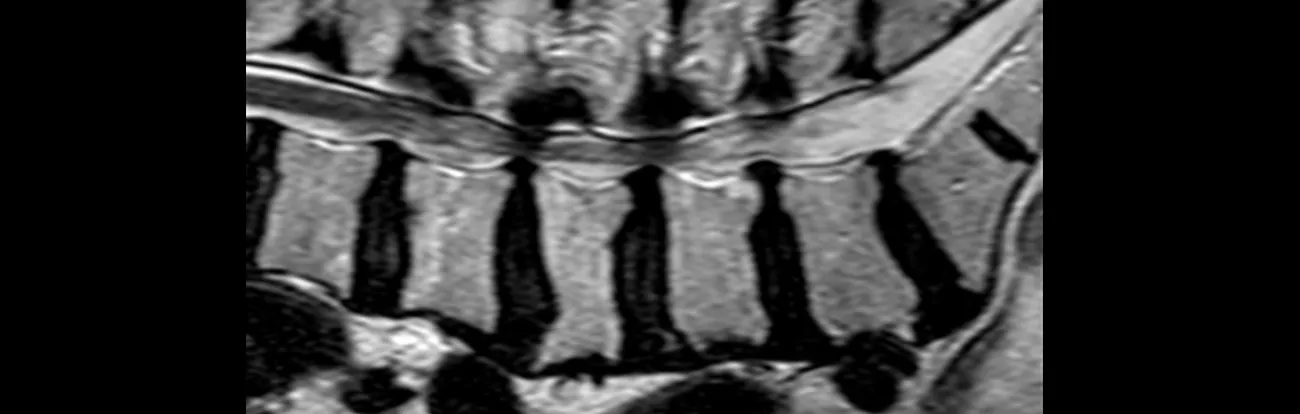

Lumbalna stenoza kanala je suženje spinalnog kanala ili tunela kroz koje prolaze živci i druge strukture povezane s tim kanalom. Suženje spinalnog kanala obično nastaje zbog promjena povezanih sa starenjem, uključujući i pomjeranje jednog pršljena iz normalnog položaja, što smanjuje veličinu kanala.

Suženje spinalnog kanala ili bočnih kanala koji štite živce obično dovodi do uklještenja korijena živca kičmene moždine. Kako se promjer kanala smanjuje, živci postaju sve više iritirani.